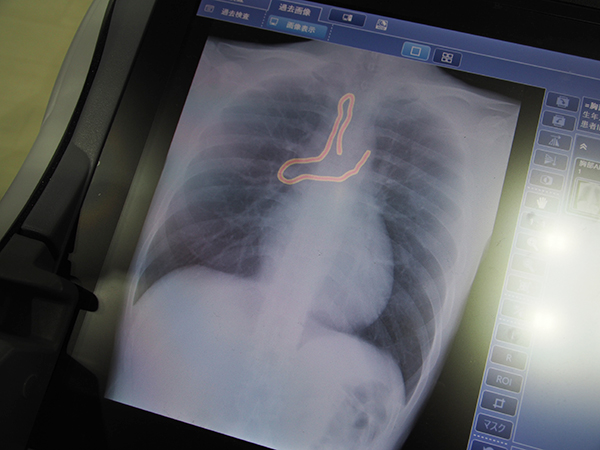

回診用X線撮影装置「MobileDaRt Evolution MX8 Version cタイプ」に搭載可能な“遺残確認支援ソフトウエアSmart DSI”は,AIの深層学習を用いて体内の異物を色づけて強調表示する。術後の遺残物の見逃し防止を支援し,効率的なチェックを可能にする。AIを用いたソフトウエアとしては,X線TVシステム「SONIALVISION G4」で提供されるトモシンセシスアプリケーション“T-smart PRO”と,腰椎骨密度測定を支援するアプリケーション“SmartBMD AI Assist”も紹介した。T-smart PROは,視認性の良い再構成画像のパラメータ設定や再構成範囲の設定をAIにより自動化することで,検査時間の短縮に貢献する。また,SmartBMD AI Assistは,深層学習を応用したAIにより迅速・高精度な骨のセグメンテーションを可能にした。従来,マニュアルで行っていた解析作業をAIで支援することで,オペレータの作業時間や手間を大幅に削減することができる。

AIの深層学習を用いた“遺残確認支援ソフトウエアSmart DSI”